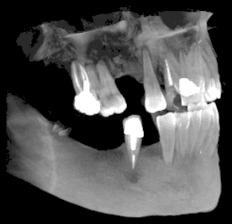

3D скенер на зъби – сектор

Чрез използването на модерната CBCT технология (Cone Beam Computer Tomography) се сканира триизмерен образ на част от челюстта, обхващаща до четири зъба. Този образ може лесно да се обработва. Разглеждането на структурата в 3-те различни равнини помага за прецизната диагностика. Изследването е подходящо за диагностициране на заболявания на зъбите, при ендодонтско лечение, както и за поставяне на единични импланти и др.